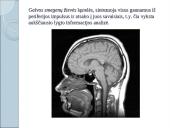

Kaip mes išmokstame ? Skaitymas - sudėtingas psichofiziologinis procesas, kuriame dalyvauja kalbinės motorikos, kalbinės klausos ir regėjimo analizatoriai. • Skaitymas – sudėtingiausia žmogaus veikla, reikalaujanti daug pastangų ir triūso. Tai lemia paties skaitymo proceso sudėtingumas, jame dalyvaujančių komponentų ir būtinų gebėjimų gausa. Mokančiajam skaityti ši veikla atrodo įprasta ir automatizuota, kad kartais tampa panašu, jog ji įgimta. Pamokos uždavinys: pasikartoje žinias apie nervų sistemą, patobulinę neuronų modelius, atlikdami jungčių (sinapsių) piešimo užduotis, mokiniai gebės nupiešti atmintį: vizualizuoti ne tik atminties produktą, bet ir patį procesą. Įsivertinimas: kiekvienas įsivertins kaip jam sekėsi piešti atmintį. • https://mokslustudija.wordpress.com/2013/07/12/kaip-atrodo-atmintis/ Sudėtingiausia gyvos materijos forma Žemėje – žmogaus smegenys Įdomūs faktai apie smegenis • Galvos smegenyse per sekundę įvyksta 100 000 cheminių reakcijų. • Ilgiausiai gyvenančios ląstelės žmoguje yra smegenų ląstelės, jos gyvena tiek pat, kiek ir žmogus. • Nuo gimimo žmogaus galvos smegenyse jau yra apie 14 milijardų ląstelių, o jų skaičius iki mirties nedidėja. Priešingai sulaukus 25 metų kasdien sumažėja 100 000 ląstelių. Per minutę miršta 70 ląstelių. Po 40 metų smegenų degeneracija padidėja, o po 50 neuronai džiūva ir jų apimtis susitraukia. • Per minutę pro smegenis prateka apie 750 mililitrų kraujo. • Smegenys sudaro tik 2 proc. viso kūno svorio, tačiau joms atitenka 20 proc. krauju pernešamų medžiagų. • Žmogaus smegenys per dieną generuoja daugiau elektros impulsų negu visi pasaulio telefonai kartu. Užduotėlė  Galvos smegenų žievės ląstelės, sintezuoja visus gaunamus iš periferijos impulsus ir atsako į juos savaisiais, t.y. čia vyksta aukščiausio lygio informacijos analizė. Nervų sistema • Tai elektrocheminės komunikacijos sistema, kuri įgalina mus mąstyti, jausti ir veikti. • Žmogus gimsta su galutinai susiformavusia nervų sistema, bet jo neurologinę brandą labai veikia aplinka, kurioje jis atsiduria po gimimo. • Raida – nenutrūkstantis procesas, prasidedantis apvaisinimu ir besitęsiantis visą individo gyvenimą. Jutimo organai – sudedamoji žmogaus sensorinių sistemų dalis. • Bet kurios sensorinės sitemos (regos, klausos, pusiausvyros, uoslės, skonio, somatosensorinės) veikla prasideda nuo jutimo organuose esančių receptorių, kurie gautą fizinę ar cheminę energiją transformuoja į nervinį impulsą ir perduoda į centrinę nervų sistemą. Centrinę nervų sistemą sudaro galvos ir nugaros smegenys. • Nervai sujungia centrinę nervų • sistemą su kitomis kūno dalimis, • visais audiniais ir organais • ir perduoda nervinius impulsus. • Nustatyta, kad gerai besivystantis gimdoje • kūdikis gimsta turėdamas 14-20 milijardų • smegenų nervinių ląstelių (neuronų). Po • gimimo nebesukuriamas nei viena neuronas, • vaikas jų niekada daugiau neįgyja. • https://thepresentation.ru/medetsina/chastnaya-gistologiya-nervnaya-sistema Pasižiūrėkime, kaip veikia mūsų nervų sistema https://www.youtube.com/watch?v=MK8fxmgrwp4 • Smegenyse esantys neuromediatoriai perduoda elektrinius signalus iš vienos nervinės ląstelės (neurono) kitai. Trūkstant neuromediatorių smegenyse sutrinka informacijos perdavimas. • Pradinėse vystymosi stadijose didieji galvos smegenų pusrutuliai turi lygų paviršių, po kurio laiko juose pradeda ryškėti vagos ir vingiai. Gimstant pagrindinės vagos ir vingiai jau būna išsivystę, tačiau galutinis išorinio pusrutulių paviršiaus, vadinamojo galvos smegenų žieve, funkcinis ir morfologinis brendimas baigiasi gerokai vėliau. • Nervų sistemos subrendimą rodo nervinių skaidulų mielinizacijos laipsnis. Kokia spalva nupieštas mielino dangalas? Padenkite „mielinu“ neurono modelį. Nervine ląstele sklinda impulsai. • Kad nervinis impulsas galėtų slinkti išilgai nervo, pirmiausia turi būti sveikos nervinės skaidulos. • Nervinės ląstelės sudaro pilkąją smegenų medžiagą. Galvos smegenų pusrutulių paviršiuje esanti pilkoji medžiaga sudaro galvos smegenų žievę. • Nervinio impulso plitimas nervų sistema taip pat tobulėja dėl besiformuojančio nervus dengiančio mielininio dangalo. Šis procesas vadinamas mielinizacija. Mielinas - tai baltymų ir riebalų gausi struktūra, apgaubianti nervines ląsteles ir jų ataugas. Mielininio dangalo pagalba sukuriamas efektyvus ir greitas informacijos perdavimas į smegenis ir iš jų. Kai embriono vystymosi sąlygos palankios, gimstant vaisiaus smegenys turi visas dalis, žievėje ryškūs pagrindiniai vingiai ir vagos. Lyginant su visu kūnu, smegenys palyginti labai didelės ir sudaro apie 12 % viso kūno svorio. O suaugusio žmogaus – tik apie 2%. Be to, naujagimio smegenyse gerai neišsivysčiusi galvos smegenų žievė, neužsibaigęs visas žievės vagų ir vingių formavimasis. Dar nėra visiškai baigtas mielinizacijos procesas. • Kai embriono vystymosi sąlygos palankios, gimstant vaisiaus smegenys turi visas dalis, žievėje ryškūs pagrindiniai vingiai ir vagos. Lyginant su visu kūnu, smegenys palyginti labai didelės ir sudaro apie 12 % viso kūno svorio. O suaugusio žmogaus – tik apie 2%. Be to, naujagimio smegenyse gerai neišsivysčiusi galvos smegenų žievė, neužsibaigęs visas žievės vagų ir vingių formavimasis. Dar nėra visiškai baigtas mielinizacijos procesas. • 7m. vaiko smegenų augimas jau žymiai lėtesnis bei pilnai baigiasi mielinizacijos procesas. Žievinės funkcijos • Galvos smegenų žievėje lokalizuojasi įvairios funkcijos (elementarių, sudėtingų gnostinių ir nespecifinių ): Broka motorinis kalbos centras, Vernike kalbos supratimo, klausos, regėjimo, uoslės, jutimų, motorikos, užimantys tam tikras smegenų žievės zonas. • Kognityvinės funkcijos negali būti lokalizuotos vienoje žievės vietoje, nes jos formuojasi ryšyje su kitomis žievės zonomis (raštas, skaitymas ir kt.). • Visą gyvenimą kol mokomės susidaro naujos sinapsės – jungtys. Įsivaizduokite, kad esate neuronai. • Kiekvienas taškas – neuronas. • Sudarykite sinapses su tam tikrais neuronais, nupieškite jungtis. Pasirinktinai atlikite užduotį: • 1.Nupieškite kaip išmokstame. • 2. Nupieškite atmintį. https://analyticalscience.wiley.com/do/10.1002/was.0004000303/ Sunku ar lengva buvo išmokti kaip išmokstame? Įsivertinkite. • Funkcijos lokalizacija galvos smegenų žievėje nėra stabili. • Ji kinta ontogenezės metu ir dėl vėlesnių treniruočių poveikio. Pažeidus vieną kurią galvos smegenų žievės dalį, jos funkcijas gali perimti greta esanti žievės zona. • Funkcijos lokalizacijos dinamiškumas ir smegenų žievės funkcinis plastiškumas vaikų amžiuje, kol smegenys yra vystymosi stadijoje – kur kas didesnis. Skiriasi naujagimio smegenys nuo suaugusio žmogaus smegenų ir savo biochemine sudėtimi. Jose daugiau vandens, aktyvesnė lipidų apykaita. Nervų sistema labai reikli deguoniui. Ji sunaudoja apie 20% viso organizmo gaunamo deguonies ir, esant nedideliam deguonies trūkumui, smegenyse vyksta dideli pakitimai. Taigi, naujagimių ir kūdikių smegenys yra labai pažeidžiamos ir tai greičiau įvyksta tada, kai smegenyse jau yra kad ir labai menkų funkcinių ar morfologinių pakitimų. • Skiriasi naujagimio smegenys nuo suaugusio žmogaus smegenų ir savo biochemine sudėtimi. Jose daugiau vandens, aktyvesnė lipidų apykaita. Nervų sistema labai reikli deguoniui. Ji sunaudoja apie 20% viso organizmo gaunamo deguonies ir, esant nedideliam deguonies trūkumui, smegenyse vyksta dideli pakitimai. Taigi, naujagimių ir kūdikių smegenys yra labai pažeidžiamos ir tai greičiau įvyksta tada, kai smegenyse jau yra kad ir labai menkų funkcinių ar morfologinių pakitimų. • Be pozityvumo ir grožio daigų negalima žmogui išeiti iš vaikystės į gyvenimą, be pozityvumo ir grožio daigų negalima išleisti kartos į kelią. F. Dostojevskis • Manoma, kad maniakine depresija sirgo Kurt Cobain, Hansas Kristianas Andersenas, Liudvikas van Bethovenas, Čarlzas Dikensas, Ernestas Hemingvėjus, Merlin Monro, Markas Tvenas, Nina Simone, Catherine Zeta-Jones ir kt. Specialieji ugdymosi poreikiai • pagalbos ir paslaugų reikmė, atsirandanti dėl to, kad ugdymo ir saviugdos reikalavimai neatitinka asmens, turinčio specialiųjų poreikių, galimybių. Sudėtingos asociacinės galvos smegenų žievės funkcijos yra praksis ir gnozis. • Praksis – gebėjimas atlikti (išmokti atlikti) sudėtingą veiksmą. Mokantis atlikti judesius (kartoti), dalyvauja regėjimo, judesio koordinavimo funkcinės sistemos, kalbos zonos ir kt. Priklausomai nuo to , kuri šios sudėtingos asociatyvinės funkcinės sistemos dalis pažeista, formuojasi įvairios apraksijos formos (afazija, oralinė apraksija, veiksmų planavimo apraksija, erdvės ir laiko suvokimo nepilnavertiškumas → suaugę negeba skaityti ir skaičiuoti , o vaikai to išmoksta labai sunkiai, konstrukcinė apraksija – vaikas gali atlikti veiksmus pagal pvz. ir pagal žodinę instrukciją, tačiau negali konstruoti (sudėti visumą iš dalių) ir kt.). Gnozis (gr. gnosis – pažinimas) yra gebėjimas sensorinėmis sistemomis (rega, klausa, lytėjimu, skoniu, uosle) pažinti pasaulio reiškinius ir įvairius objektus • Gnozis kaip ir praksis, formuojasi sąveikaujant sudėtingoms sensorinėms sistemoms. Esant tam tikrai agnozijai sutrinka, ar yra nepakankamas ar visai išnyksta gebėjimas atpažinti (akustinė, uoslės ir skonio, astereoagnozija (neatpažįsta objektų čiuopdami) ir kt.). • Sudėtingi žmogaus gebėjimai, pavyzdžiui, kalba, priklauso nuo darnios smegenų sričių veiklos. Nustatyta, kad pažeidus bet kurią iš kelių žievės zonų, išryškėja afazija – sutrinka kalba. Keista tai, kad vieni žmonės gali sklandžiai kalbėti, bet negali skaityti (nors puikiai mato), o kiti – supranta, ką skaito, bet negali kalbėti. Dar kiti gali rašyti, bet negali skaityti; gali skaityti, bet negali rašyti; gali skaityti skaičius, bet ne raides; gali dainuoti, bet negali šnekėti. Tai lemia pažeidimo vieta. 1.Intelekto sutrikimas: nežymus, vidutinis, žymus, labai žymus, nepatikslintas intelekto s. • Intelekto sutrikimą turinčių vaikų bruožai: • 1. Sumažėjęs gebėjimas mokytis ir išmokti ( nepilnavertė atmintis, nepakankamas gebėjimas diferencijuoti ir asocijuoti, negebėjimas abstrakčiai mąstyti, negebėjimas numatyti mokymosi strategijas). • 2. Dėmesio nesukaupimas (vyrauja nevalingas dėmesys, tikslingoje veikloje jiems būdingas išsiblaškymas. Dėmesį išlaikyti įmanoma, tik nuolat naudojant ryškius išorinius stimulus). • 3. Kalbos neišsivystymas ir kalbėjimo sutrikimai. Kalbiniai gebėjimai dažnai būna menkesni ir neatitinka psichinio vaikų amžiaus. Artikuliacijos sutrikimai vaikams, turintiems protinę negalią, yra būdingesni nei normaliai besivystantiems vaikams. Kalbos vystymosi vėlavimas gali siekti 3-4 metus. 4. Sutrikę visi atminties procesai: įsiminimas, išlaikymas, atpažinimas, atgaminimas (ypatingai sunkiai įsimena abstrakčią sudėtingą medžiagą. Medžiagą reikia pateikti vaizdžiai, įdomiai, ryškiai, o ne žodžiu) • 4. Sutrikę visi atminties procesai: įsiminimas, išlaikymas, atpažinimas, atgaminimas (ypatingai sunkiai įsimena abstrakčią sudėtingą medžiagą. Medžiagą reikia pateikti vaizdžiai, įdomiai, ryškiai, o ne žodžiu) • 5. Sensorinių sistemų pažeidimai. Po CNS pažeidimo sensorinių sistemų raidos sutrikimai gali būti vienas pirmųjų proto negalės požymių. Sensorinių sistemų pažeidimai būdingesni vidutinę ir žymią proto negalę turintiems vaikams. • 6. Savitvarkos įgūdžių susidarymo sutrikimai. Šios raidos sferos nepilnavertiškumas būdingesnis vidutinę ir žymią proto negalę turintiems vaikams. 7. Socialinių įgūdžių, ypač, bendravimo, stoka. Šios raidos sferos nepilnavertiškumas būdingas vidutinę ir žymią proto negalę turintiems vaikams. • 7. Socialinių įgūdžių, ypač, bendravimo, stoka. Šios raidos sferos nepilnavertiškumas būdingas vidutinę ir žymią proto negalę turintiems vaikams. • 8. Paties sudėtingiausio – mąstymo – proceso neišsivystymas (ilgą laiką mąstymas išlieka vaizdinis – veiksminis). Analizuodami daiktus pastebi labai mažai daikto savybių ar sudėtinių dalių, lygindami nenustato santykių tarp dviejų objektų, vardina kiekvieno daikto požymius. Negeba apibendrinti. Mąstymui būdingas inertiškumas, lėtumas, siaurumas, paviršutiniškumas, nekritiškumas. Šios savybės išlieka visą gyvenimą. Mąstymas – tai veiksmai vykstantys su vaizdiniais arba sąvokomis. 9. Valios ir emocijų ypatumai (jiems būdingas emocinis nesubrendimas, pasireiškiantis jausmų primityvumu, nepakankamu diferencijuotumu (arba linksmas, arba liūdnas, arba viskas gerai, arba viskas blogai); kartais neadekvatumu konkrečiai situacijai, staigia nuotaikų kaita, sunkiu ir lėtu aukštųjų dvasinių jausmų formavimusi ir kt). • 9. Valios ir emocijų ypatumai (jiems būdingas emocinis nesubrendimas, pasireiškiantis jausmų primityvumu, nepakankamu diferencijuotumu (arba linksmas, arba liūdnas, arba viskas gerai, arba viskas blogai); kartais neadekvatumu konkrečiai situacijai, staigia nuotaikų kaita, sunkiu ir lėtu aukštųjų dvasinių jausmų formavimusi ir kt). • 10. Fizinis vystymasis gali atitikti visas normas, bet gali vaikas turėti ryškių fizinio vystymosi sutrikimų. 1.6. Įvairiapusiai raidos sutrikimai (pasireiškia kokybiniais socialinio bendravimo ir komunikacijos sutrikimais bei ribotu, stereotipiniu ir pasikartojančiu interesų ir veiklos pobūdžiu) • 1.vaikystės autizmas • 2.atipiškas (netipiškas) autizmas • 3.Rett’o sindromas • 4.Asperger’io sindromas • 5.kiti įvairiapusiai raidos sutrikimai • Dažniausiai raida būna sutrikusi nuo kūdikystės, išimtinais atvejais išryškėja per pirmuosius penkerius metus. II.Mokiniai, turintys specifinių mokymosi sutrikimų • Jiems reikalingas ilgalaikis specialusis ugdymas ir g.b. skiriamos psichologo, socialinės ir/arba medicininės paslaugos. 2.Mokiniai, turintys mokymosi sutrikimų • 2.1.Bendrieji mokymosi sutrikimai (buvęs ribotas intelektas) • Tai ribinė zona tarp normalių sugebėjimų ir intelekto sutrikimo. Šių asmenų intelekto IQ yra tarp 70-79. Intelekto ribotumas pasireiškia elgesio sunkumais, mokymosi motyvacijos, bendraisiais, specifiniais mokymosi sunkumais (iš dviejų ir daugiau dalykų), savireguliacijos sutrikimais, bendru vaiko raidos sulėtėjimu ar įvairiais šių problemų deriniais. 2.1.2.Specifiniai mokymosi sutrikimai • Mokymosi sutrikimai konstatuojami, kai: • Bendrieji intelektiniai mokinio gebėjimai pakankami, tačiau labai netolygiai susiformavę, pasireiškia mažesniais skaitymo, rašymo ar matematikos mokymosi pasiekimais; • Būdingi ryškūs specifiniai vieno ar kelių pažinimo procesų ar savireguliacijos sutrikimai, kurie trukdo mokiniui visaverčiai naudotis savo potencinėmis galimybėmis – gerai susiformavusiais intelektiniais gebėjimais; Esant mokymosi sutrikimams • Gali išryškėti gilus akademinis atsilikimas – realūs mokinio mokymosi pasiekimai prastesni, nei būtų galima prognozuoti pagal intelektinių gebėjimų lygį; programinis atsilikimas gali būti vieneri dveji metai, o itin netinkamomis aplinkybėmis ir daugiau; • Jiems būdinga neryški neurologinė simptomatika, kuri ir yra specifinių pažinimo procesų ar savireguliacijos sutrikimų priežastis. • Rašymo sutrikimai (rašymas - sudėtingas kalbinės veiklos procesas, kuriame dalyvauja kalbinė klausa, kalbinė motorika, regėjimas bei smulkioji rankų motorika). • Rašymo sutrikimo priežastis – galvos smegenų žievės kalbinių zonų patologija, tačiau daug rašymo trūkumų atsiranda ir dėl silpno suvokimo klausa bei rega, neišsivysčiusios kalbos. Viena iš disgrafijos priežasčių gali būti ir paveldėjimas. Matematikos mokymosi sutrikimai • Pagrindinių matematinių įgūdžių sunkumai (skaičiavimo, aritmetinių veiksmų žodžiu bei jų užrašymo raštu, daugybos lentelės įsiminimo sunkumai); • Matematinių terminų (sąvokų) pavadinimo ir suvokimo, žodžiu pateiktų užduočių užrašymo skaičiais sunkumai; • Skaitmenų, matematinių ženklų, skaičių, simbolių suvokimo, skaičių užrašymo sunkumai; • Tekstinių uždavinių sprendimo sunkumai ir t.t. Neverbaliniai mokymosi sutrikimai • Sutrikimo pagrindas – neverbalinės informacijos apdorojimo sunkumai. • Tai sindromas, o ne pavieniai požymiai. • Pagrindiniai trūkumai: prastesni neverbaliniai gebėjimai; sensorinės integracijos sunkumai; sutrikęs regimojo skyrimo ir vizualinių detalių atpažinimo; regimieji erdviniai ryšiai; motorinės koordinacijos trūkumai. Neverbaliniai mokymosi sutrikimai • Jie ilgai neišmoksta skaityti, rašyti, skaičiuoti ir tuo atrodo panašūs į sutrikusio arba bendrųjų mokymosi sutrikimų turinčius vaikus, nors tokie nėra. Vaikai sunkiai ir netiksliai atpažįsta, skiria, interpretuoja arba įsimena matomus vaizdus, simbolius (pvz., raides, skaičius, formas, schemas, diagramas, žemėlapius ir kt.); • Verbaliniai gebėjimai aukštesni ar aukštesni nei vidutiniai ir verbalinis IQ reikšmingai aukštesnis nei neverbalinis IQ. Kaip pasireiškia neverbaliniai mokymosi sutrikimai? • Skaitymo, rašymo, matematikos ir kt.dalykų mokymosi sunkumai: • Sunkiai įsimena raides, nes “neaiškiai” suvokia jų formą, nepastebi smulkių skirtumų (n-m, l-t, I-J…); • Painioja optiškai panašias, tik skirtingai erdvėje orientuotas raides (p-b-d, n-u); • Sunkiai jungia jas į skiemenis ir skiemenis į žodžius, ne visada pasiekia patenkinamos skaitymo technikos, tačiau perskaityto žodžio prasmę suvokia. • Kartais geriau rašo nei skaito; geriau pažįsta rašytines raides nei spausdintines (rašant prisideda papildomas rankos padėties ir judesių jutimas, kuris pagerina raidės formos suvokimą); • Kopijuoja, perkoduoja taip pat prastai kaip ir rašydami diktuojamą tekstą; Kaip pasireiškia neverbaliniai mokymosi sutrikimai? • Gali daryti veidrodinio apvertimo klaidų, netiksliai rašo pačias raides, nepaiso eilučių, jų rašysena negraži; • Dažnai raides sukeičia vietomis (at-ta, ap-pa); • Nejaučia sakinio, žodžio ribų (nors žodinės kalbos vienetus skiria gerai). • Mokydamiesi matematikos, mokiniai painioja skaitmenis (6-9), ženklus (>,